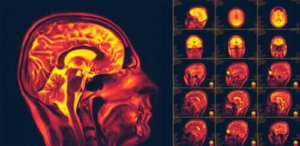

Hjärnans neuroplasticitet, även känd som cerebral plasticitet, är en av de viktigaste upptäckterna om människokroppen. Det är hjärnans förmåga att ändra och anpassa sig till nya beteenden eller upplevelser.

Neuroplasticitet är neuronernas förmåga att regenerera. De gör detta både anatomiskt och funktionellt. Det är faktiskt en process som involverar många biokemiska och metaboliska reaktioner. Det betyder också att hjärnan har stor anpassningspotential.

Neuroplasticitet avser hur vårt nervsystem kan skapa nya kopplingar. Det gör det som respons på ny stimuli, information, eller även för att läka skador i gamla kopplingar.